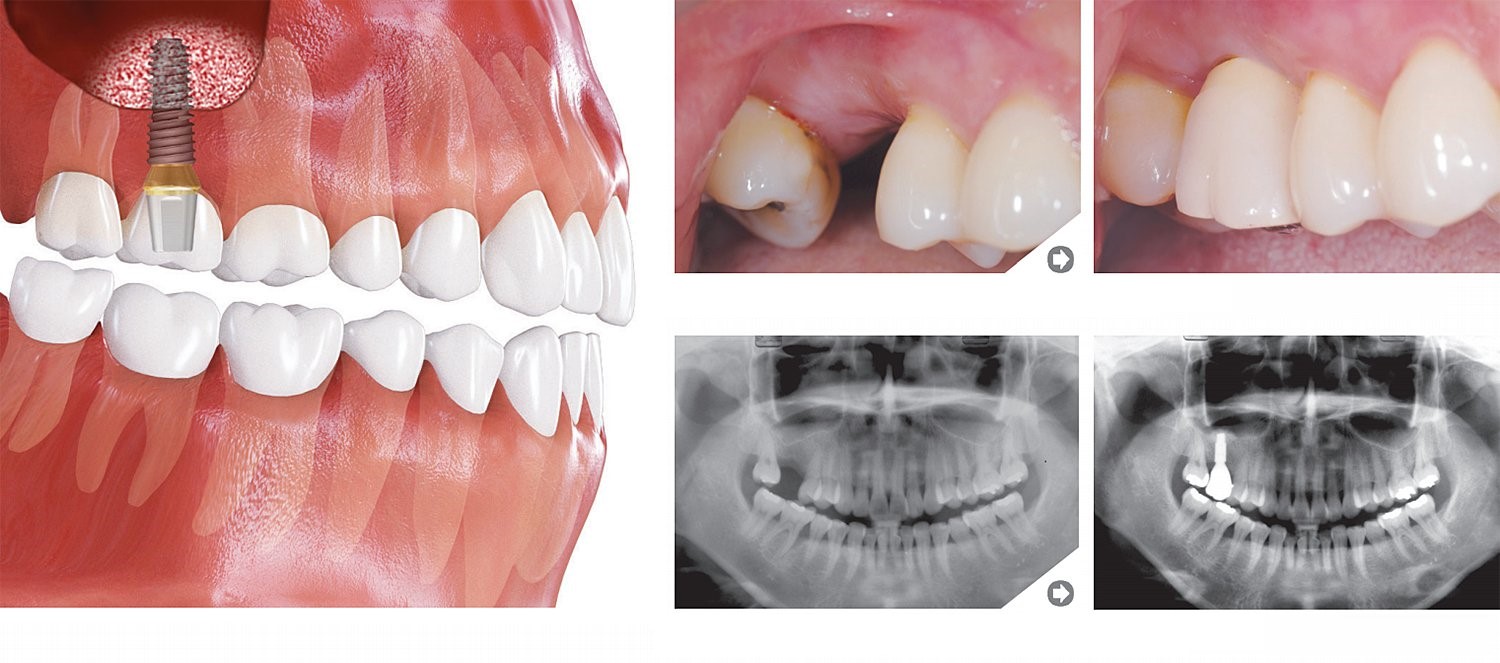

Trūkst viena zoba

Priekšējais zobs

Apakšējais molārs

Implantācija šaurā starpzobu telpā